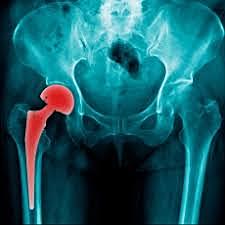

ARTROPLASTIA ACTUAL

Se continua investigando en la actualidad la mejora de los reemplazos, así mismo en la ultima actualización de las protesis, se implementan nuevos elementos como cromo, cobalto,ceramicos y el anteriormente mencionado cemento oseo para la fijacion, asi mismo un vastago mas largo y mejor adaptable